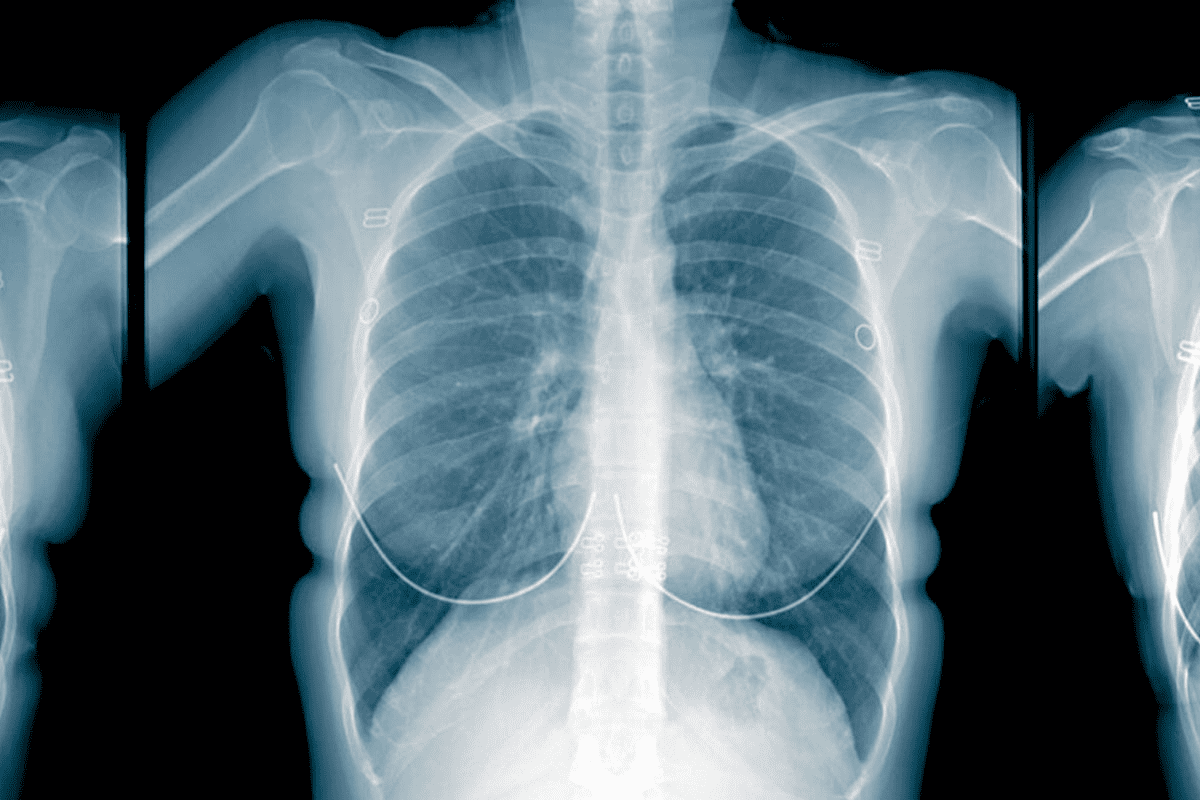

A precise cancer diagnosis is essential for creating an effective treatment plan. The process begins with a physical exam and a review of medical history. While imaging tests like CT scans, MRIs, and PET scans provide images of a tumor’s size and location, a biopsy is the definitive diagnostic tool. This involves removing a small tissue sample for a pathologist to examine. Blood tests may also be used to detect tumor markers. This collective data is then used to “stage” the cancer, a critical step that determines the extent of the disease.

• Imaging Tests: CT, MRI, and PET scans produce detailed images of organs and tissues to detect tumors and measure their size.